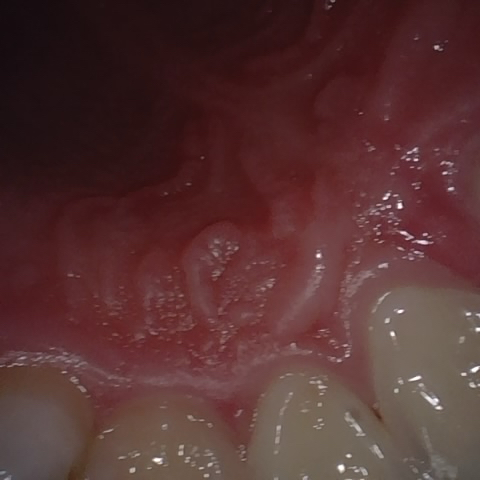

NHD39990

Annotated as "Good"